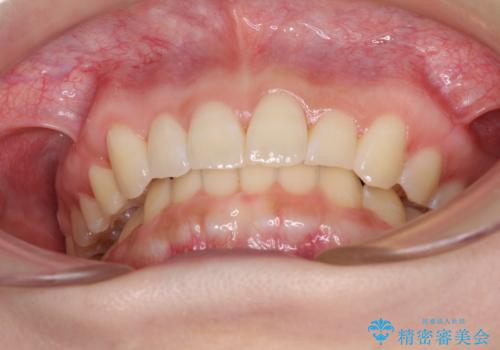

上下顎ともに歯列全体の後方移動とIPR(歯と歯の間を削る)によってデコボコが解消するように設計し、インビザラインにより治療を行うこととしました。

強い咬合力による臼歯部の噛みにくさと、それに伴う歯の移動の鈍さに悩まされ、非常に長い期間を要することとなりました。

上下正中位置は、治療開始時よりは改善したものの、ここが限界であろうというところでのゴールとなりました。